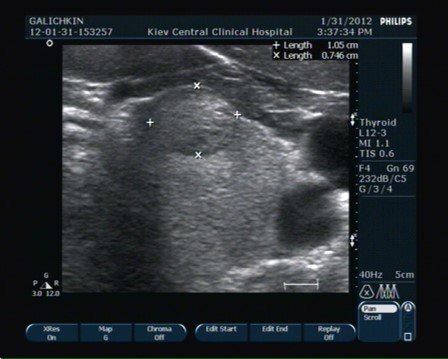

Ну що ж, почнемо з того, що таке УЗД щитовидки? Це дослідження, яке дозволяє візуалізувати структуру щитовидної залози. Щоб отримати точний результат, важливо дотримуватись певної підготовки. І тут з’являється питання про їжу.